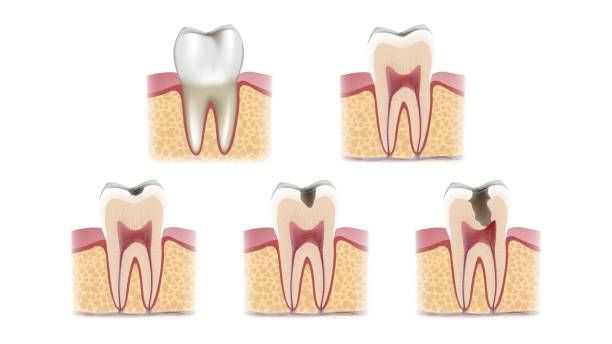

شاید فکر کنید که بعد از عصبکشی، دندان دیگر مرده است و نباید عفونت کند. اما اینطور نیست! ریشه اصلی آبسه، معمولاً باقیماندن باکتریها در کانالهای ریشه یا نشت مجدد آنها به داخل دندان است. این باکتریهای سمج، میتوانند در شکافهای میکروسکوپی، کانالهای فرعی یا حتی بخشهایی که در حین درمان به خوبی پاکسازی نشدهاند، پنهان شوند. با گذشت زمان، این موجودات ریز شروع به تکثیر میکنند و سیستم ایمنی بدن شما هم برای مقابله با آنها وارد عمل میشود. نتیجه این نبرد، تجمع چرک و التهاب است که همان آبسه معروف خودمان میشود. چیزی که از بیرون شاید یک ورم کوچک به نظر برسد، از داخل یک داستان بزرگ عفونی است.

بسیاری از ما تجربه عصبکشی را داریم، یا حداقل کسی را میشناسیم که این درمان را انجام داده است. اما آیا میدانید پشت این واژه ساده، چقدر ظرافت و دقت نهفته است؟ درمان ریشه یا اندودانتیکس، فرآیندی پیچیده برای نجات دندانی است که مغز آن (پالپ) دچار عفونت یا التهاب برگشتناپذیر شده. هدف اصلی این درمان، پاکسازی کامل سیستم کانال ریشه از باکتریها و بافتهای عفونی، شکلدهی و سپس پر کردن آن با مواد زیستسازگار است تا از ورود مجدد باکتریها جلوگیری شود. ساده به نظر میرسد، نه؟ اما در واقعیت، کانالهای ریشه مثل هزارتویی هستند با انشعابات و زوایای پنهان که دسترسی به تمام آنها واقعاً یک چالش بزرگ است.

بزرگترین چالش در درمان ریشه، همین دسترسی و پاکسازی کامل است. دندانپزشک باید مطمئن شود که هیچ باکتری یا بافت عفونی کوچکی در هیچ گوشه و کناری باقی نمانده باشد. کوچکترین غفلت میتواند منجر به آبسه بعد عصب کشی شود. تصور کنید یک سیستم پیچیده را که باید بدون دید مستقیم و فقط با تکیه بر حس و ابزارهای بسیار ظریف، کاملاً تمیز کنید. اینجاست که اهمیت ابزارهای پیشرفته و دقیق به چشم میآید. کانالهای دندان ممکن است بسیار باریک، خمیده یا حتی در بعضی موارد، کلسیفیه (سختشده) باشند که این موضوع کار را برای ابزارهای سنتی بسیار دشوار میکند.

یکی از مهمترین اجزاء، استاپرهای جراحی هستند. اینها چیزی نیستند جز ابزارهایی برای کنترل دقیق عمق حفاری. چرا اینقدر مهم است؟ چون حفاری بیش از حد میتواند به بافتهای اطراف دندان آسیب بزند یا حتی باعث پرفوراسیون (سوراخ شدن ناخواسته) شود. هر آسیبی، خودش دریچهای برای ورود باکتریها و ایجاد عفونت است. با استاپرهای 3A، دندانپزشک مطمئن میشود که دقیقاً به عمق مورد نیاز رسیده و نه بیشتر. سپس نوبت به رچت آچار ترکمتر میرسد. این وسیله کنترلشده، برای اعمال نیروی دقیق هنگام جایگذاری فیکسچرها (مثل ایمپلنت) یا حتی در بستن اسکروها در درمان ریشه کاربرد دارد. نیروی استاندارد و یکنواخت، از ترکخوردگی دندان و فشارهای اضافی که میتوانند به مرور زمان مشکلساز شوند، جلوگیری میکند.

در ادامه، دریل اکستنشن را داریم که مثل یک معجزه برای دسترسی به کانالهای ریشه عمیق و دشوار است. تصور کنید کانال ریشهای که در انتهای فک قرار دارد و دسترسی به آن با ابزارهای معمولی چقدر سخت است. این دریل با طراحی خاص خود، کمک میکند تا دندانپزشک بدون ایجاد فشار یا آسیب به بافتهای اطراف، به راحتی به تمام نقاط کانال دسترسی پیدا کند و پاکسازی را با دقت بیشتری انجام دهد. و در آخر، هندپیس جراحی 20:1 که یکی از پرکاربردترین ابزارها در کیت است. این هندپیس، سرعت چرخش را به شدت کاهش میدهد در حالی که گشتاور را بالا میبرد. نتیجه؟ دقت فوقالعاده در برش و شکلدهی، حداقل تولید حرارت (که برای سلامت بافتهای اطراف حیاتی است) و کاهش چشمگیر خطر آسیب به دندان. با این ابزارها، پاکسازی کامل و دقیق کانالهای ریشه دیگر یک آرزو نیست، بلکه یک واقعیت دستیافتنی است که مستقیماً در کاهش عفونتهای پس از درمان مؤثر است.